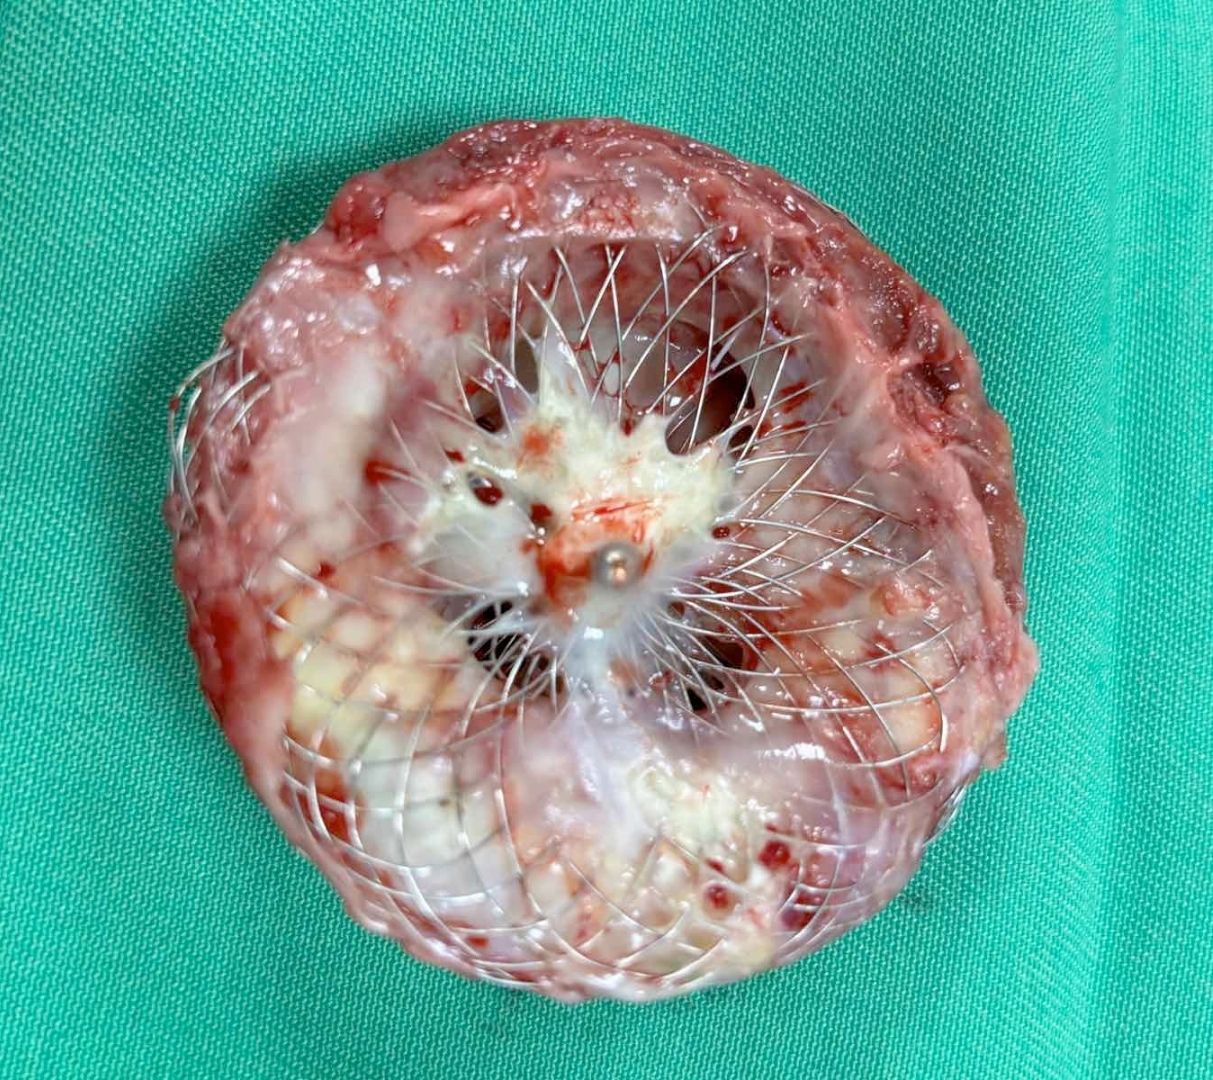

Khi đó, ê-kíp đã tiến hành bít lỗ thông bằng dụng cụ kích thước lớn. Thủ thuật thành công, bệnh nhân hồi phục tốt, siêu âm cho thấy lỗ thông được bít kín hoàn toàn, áp lực động mạch phổi giảm rõ rệt.

Theo PGS.TS.BS Nguyễn Lân Hiếu, việc dụng cụ đã nằm ổn định trong tim suốt 4 năm nhưng lại “thủng” ở giữa là tình huống cực kỳ hiếm. Theo lý thuyết, sau khoảng 6 tháng, dụng cụ sẽ được nội mạc tim bao phủ hoàn toàn, gần như “hòa vào” cấu trúc tim và không thể xảy ra hiện tượng này.

Thủ thuật được tiến hành với kỹ thuật tạo vòng loop động – tĩnh mạch, đưa dụng cụ Vascular plug II kích thước 12 mm vào bít kín hoàn toàn lỗ thủng. Toàn bộ quá trình diễn ra trong khoảng 1 giờ.